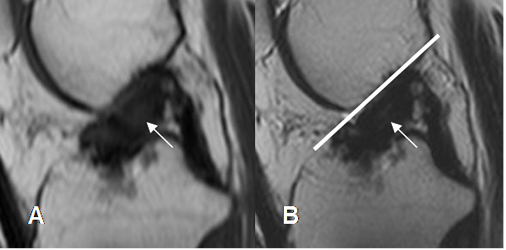

Fig 130. Túnel femoral normal.

A: Rx lateral y B: RM sagital en T1. Orientación normal del túnel femoral, en la parte posterior del cóndilo femoral.

Fig 131. Túnel femoral normal.

A: Rx AP y B: RM coronal en T1. Orientación normal del túnel femoral, dirigido hacia la 1, de las manecillas del reloj.

Fig 132. Mala orientación del túnel femoral.

A: Rx lateral. Túnel muy vertical y ocupando la parte media del cóndilo.